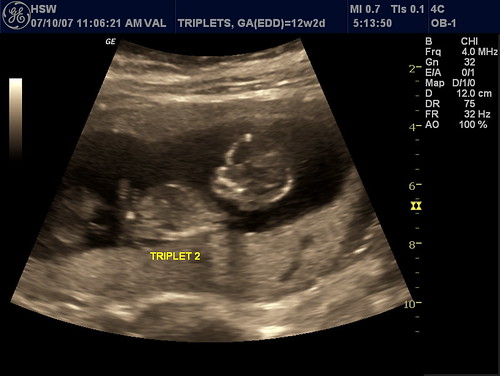

Does your “real” doctor know about your extracurricular ultrasounds? Just asking.. v. jealous that we don’t have more pics of inutero Emily.. They look like girls to me.